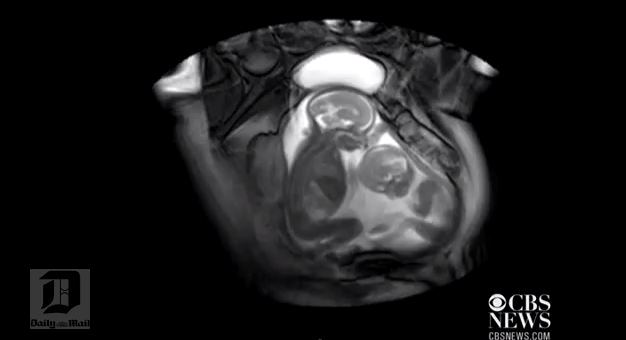

Uma imagem impressionante foi flagrada pelos médicos esta semana. Durante exame, dois bebês disputam o espaço dentro da mãe. Assista ao vídeo.